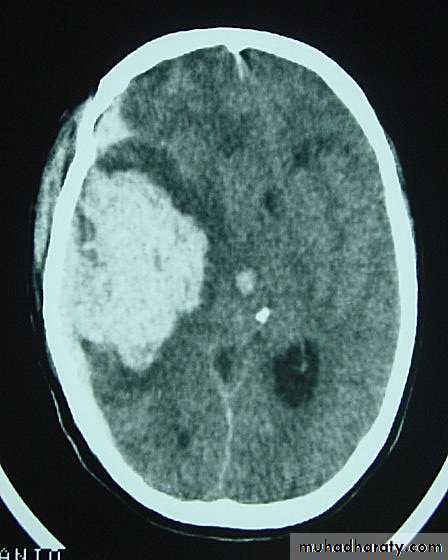

c. Intracerebral Haematoma

This is the least common of traumatic haematoma.

They are due to areas of traumatic contusion coalescing into a contusional haematoma.

Disrupted cerebral tissue release thromboplastins that potentiate haemorrhage.

CT scan: appear as hyperdence lesions with associated mass effect and midline shift.

Large intracerebral haematomas should be evacuated unless the patient’s neurological state is improving.

Small inracerebral haematomas may not require removal, but be aware that they can expand.